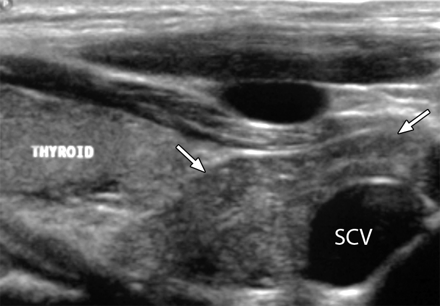

In older children, the echo pattern of the thymus appears as a fine mixture of remaining lymphoid tissue and fat. The cervical component of the thymus, which is occasionally detected with US, shows distinct hyperechoic foci that resemble a starry sky (Fig 3 , 7).

Нормальная эхоструктура шейного компонента тимуса у 7 -летней девочки расположенная справа от дуги аорты. Пациент был направлен на КТ, с подозрением на надключичное образование. На УЗИ в нижней части шеи визуализируется нормальный тимус (стрелки ), который имеет гетерогенную эхоструктуру и гипоэхогенную относительно щитовидной железы. SCV = подключичная вена